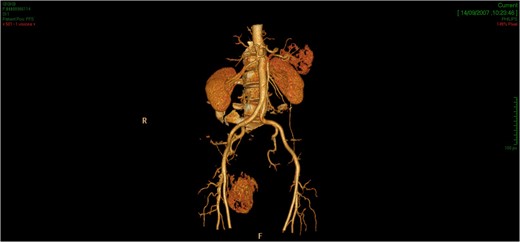

CT showed an hyperintense and inhomogeneous solid lesion taking up the right ischiorectal fossa (maximum diameter of about 10 cm), extended cranially until impressing the wall of the rectal ampulla, with no apparent infiltration (Figs 2 and 3). The lesion presented an intense contrast enhancement, sign of a rich vascularization (Fig. 4).

The tridimensional reconstruction shows the rich vascularization of the neoplasm.